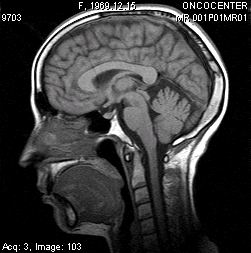

Всем пациентам в процессе курса и после брахитерапии проводили МРТ контроль в ранние сроки. Уже на 10-15 сутки после курса терапии наблюдали изменения МРТ структуры и размеров опухоли. При этом перифокальный отёк был выражен минимально ввиду особенности метода и точного подведения дозы. В дальнейшем КТ или МРТ контроль проводили через 1, 3, 6, 12 месяцев.

Описываем клинический случай стереотаксической брахитерапии, выполненной в Уральском межтерриториальном нейрохирургическом центре (ГБУЗ СО Свердловский областной онкологический диспансер), пациентке К. 31 год с глиальной опухолью диэнцефальной области (дна III желудочка). Данные МРТ головного мозга представлены на слайдах.

7. МРТ контроль спустя 4 месяца после брахитерапии. Отмечается положительная динамика в виде регресса опухоли.